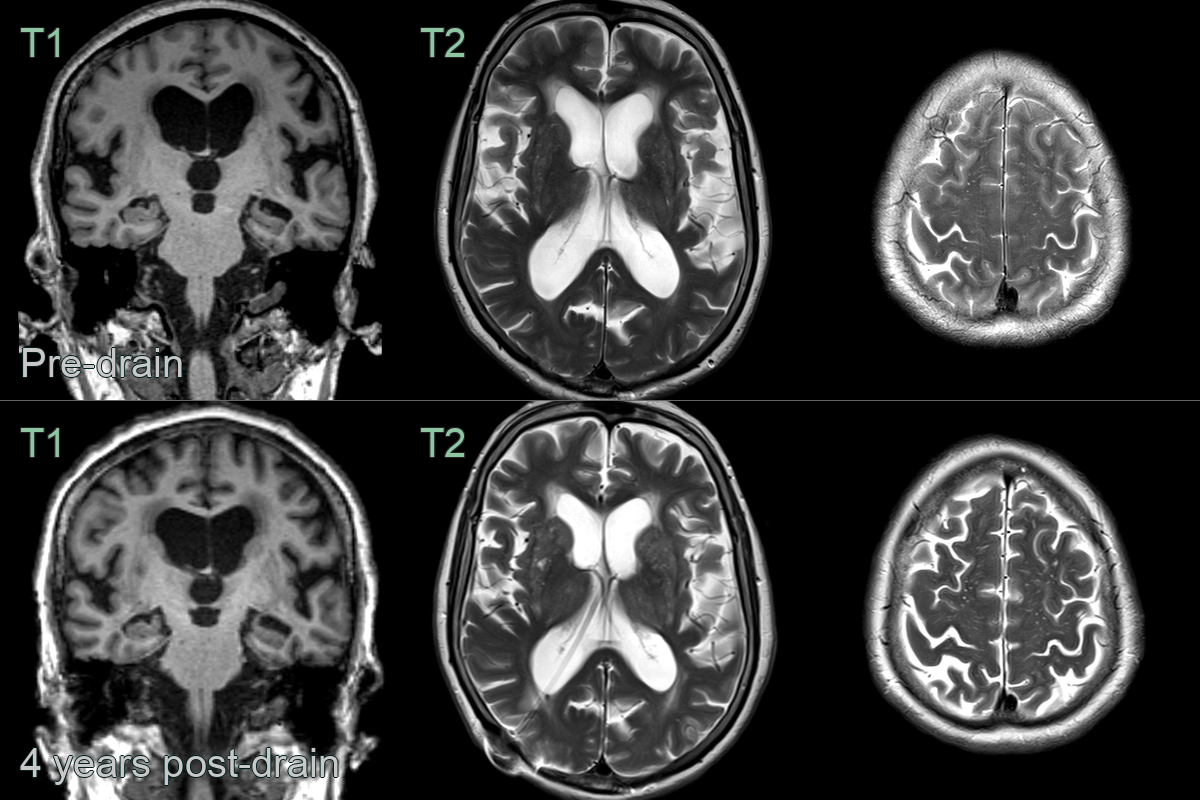

• An 80-year-old patient presented with progressive gait and cognitive syndrome.

• Four years after the insertion of a shunt, effacement of sulci at the vertex and the widening of the sylvian fissures improved.